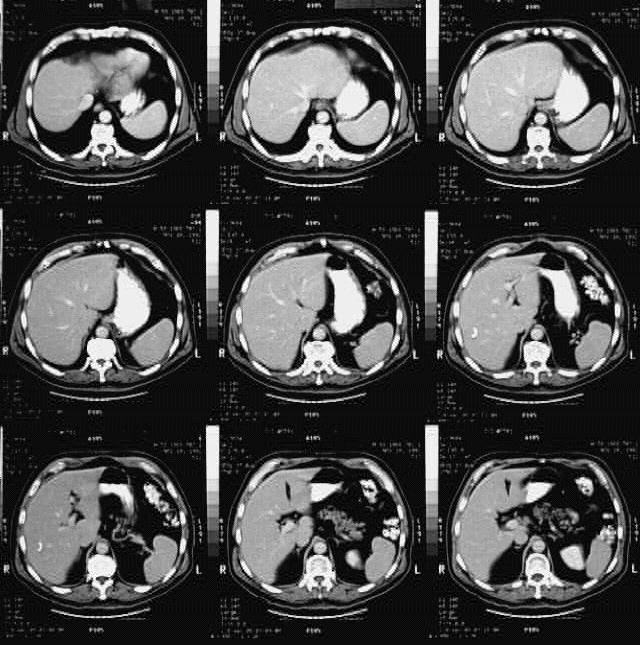

Radiology Images

Abdomen- Abdominal CT :